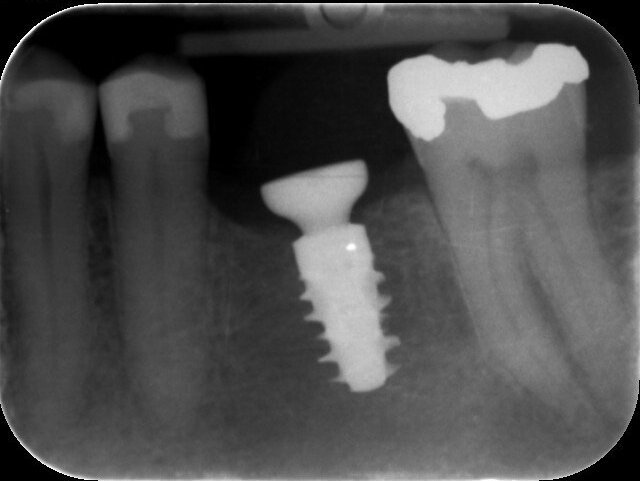

One year after the treatment, the patient reports complete satisfaction with both his chewing function and the overall aesthetics (Figs. 20 & 21). Radiographs confirm that the molar site is stable and healthy (Fig. 22). In this first human case, use of the Straumann BLX wide base implant delivered efficient and reliable performance, even in soft bone with early loading conditions.

Fig. 22: One-year follow-up radiograph.